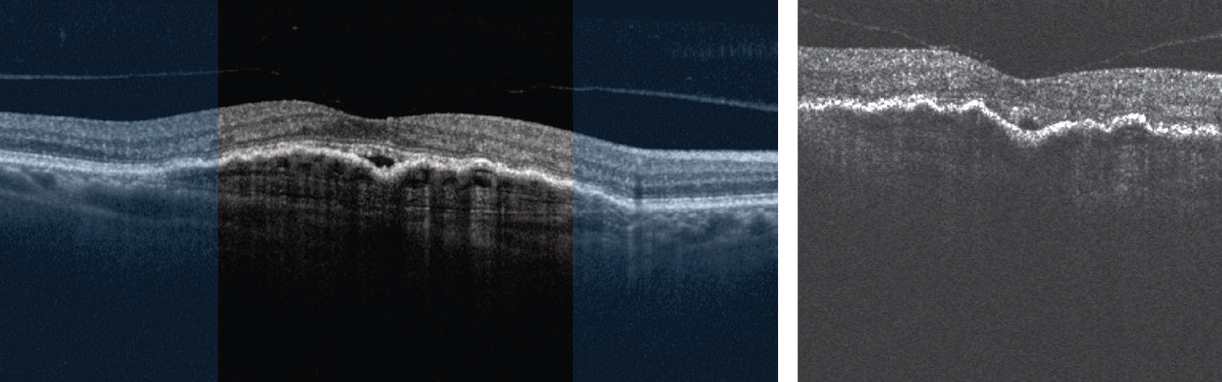

All 15 patients completed the study. Ninety-five percent of the scans were obtained successfully. Among all the acquired scans, an average of 76 scans, or 93 percent, were eligible for fluid grading analysis by the Notal OCT Analyzer or NOA (Figure). The study used a manufacturer signal quality index (MSI) to quantify image quality. The average MSI among all home-acquired scans was 4.5 (±1.1), and 97 (±6) percent of scans had MSI >2, the recommended threshold for satisfactory imaging. Over the course of the study, the duration of the self-imaging sessions decreased from a median of 45.4 to 38 seconds to scan a single eye.

| Image quality comparison of in-office Heidelberg Engineering Spectralis optical coherence tomography scan (left) and patient-operated unsupervised, at-home self-imaging with Notal Home OCT (right and below). |